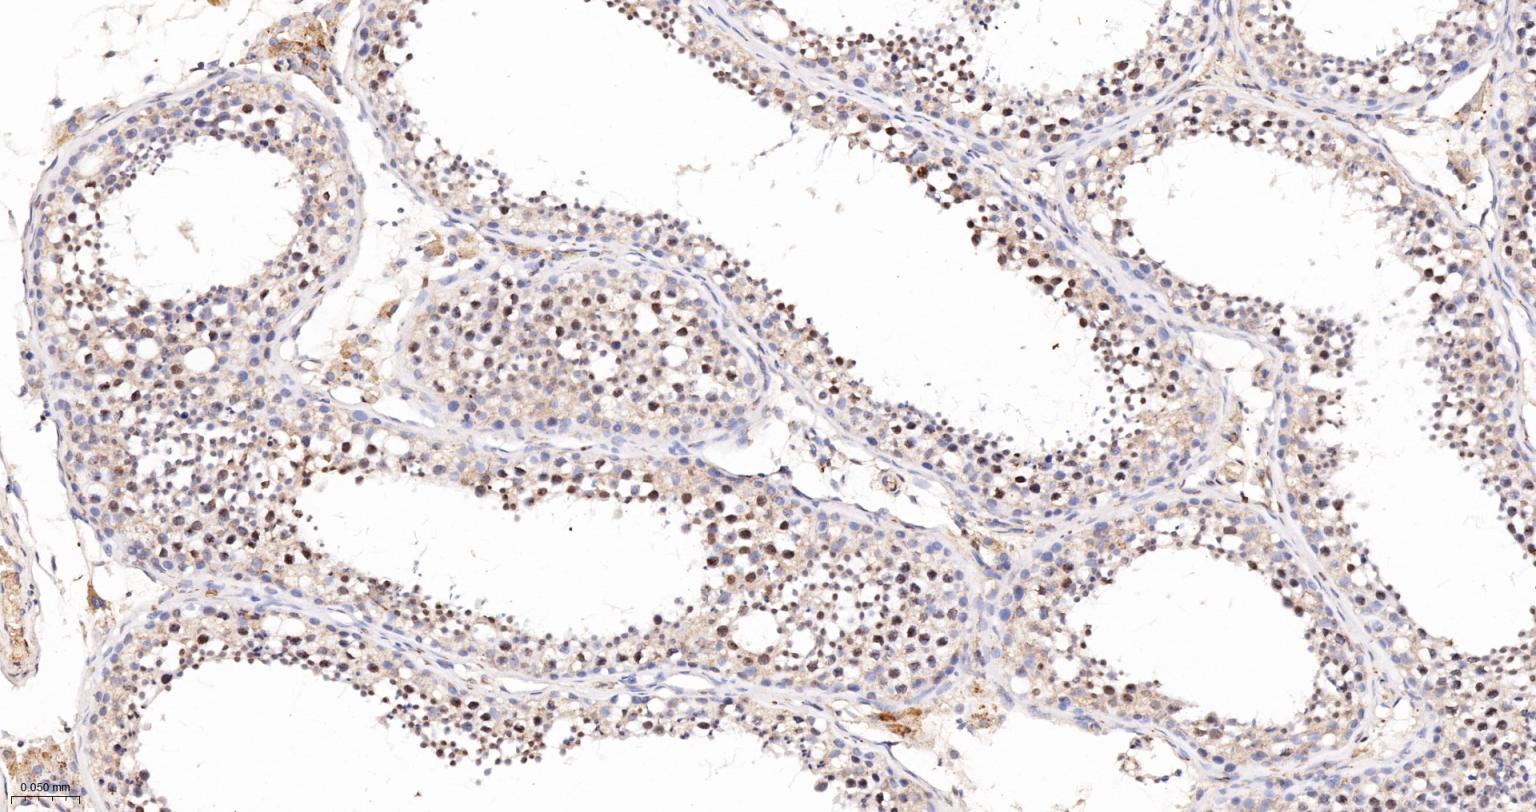

Paraformaldehyde-fixed, paraffin embedded (Human kidney); Antigen retrieval by boiling in sodium citrate buffer (pH6.0) for 15min; Block endogenous peroxidase by 3% hydrogen peroxide for 20 minutes; Blocking buffer (normal goat serum) at 37°C for 30min; Antibody incubation with (Phospho-SIRT1 (Ser47)) Monoclonal Antibody, Unconjugated (bsm-54566R) at 1:200 overnight at 4°C, followed by operating according to SP Kit(Rabbit) (sp-0023) instructionsand DAB staining.